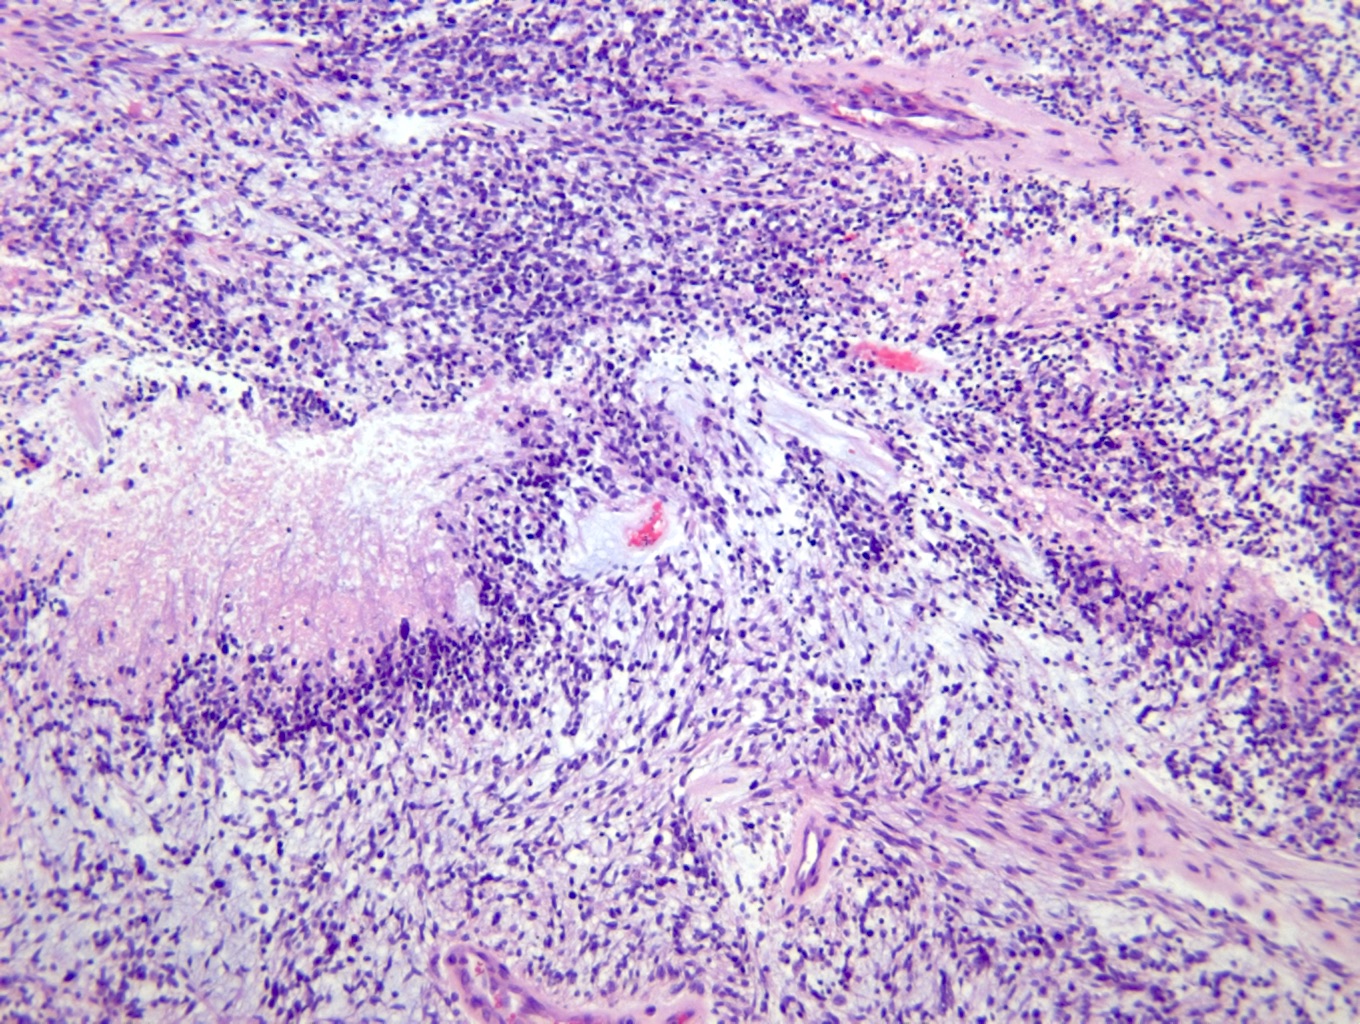

Микрофотографии гистологии глиобластомы головного мозга